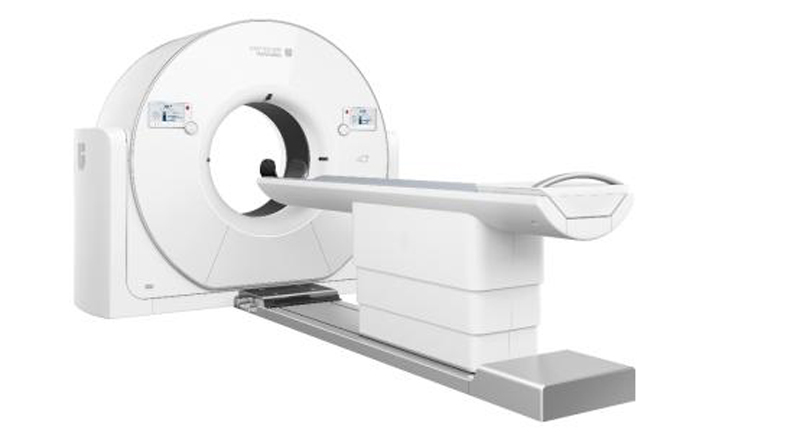

天河640是上海联影医疗科技股份有限公司自主研发生产的中国首台超高端640层CT。搭载长轴覆盖范围16厘米的320排宽体探测器,可为临床提供更高分辨率、更佳信噪比的图像;业内最快的0.25秒/圈机架转速,从影像链根源提升系统的时间分辨率,不仅能够显著提升心血管成像效果,在大范围血管成像、全脏器灌注成像和功能评估方面,也表现出显著的优势;AI赋能的智能检查流程,智能推荐扫描位置、扫描角度和重建视野,为每位患者定制扫描方案,适应不同场景的扫描范围需求。

业内最大的82厘米机架孔径,±30°机架倾斜范围,配合60kV超低千伏扫描、AI智能剂量调制、最新迭代算法等复合剂量控制技术, 为患者提供舒适、低剂量的检查体验。天河640 CT可实现单心动周期内无限心率和心律的冠脉成像、4D一站式卒中检查、恶性肿瘤功能成像、微剂量体检筛查、全速急诊方案等,代表了当前CT设备的先进技术水平。